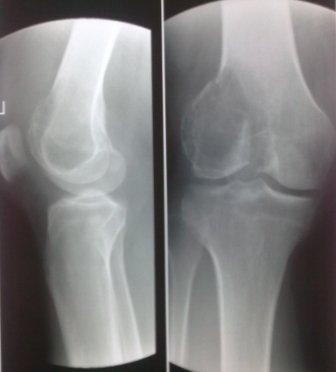

Уважаемые коллеги! Добрый вечер! Обратился мужчина 32 лет с жалобами на боли в обл. внутреннего мышелка левого бедра. Боли беспокоят около шести месяцев, лечился дома всякими мазями и т.д. 2 неделя назад упал , и после этого боли с каждым днем усиливаются. Местно определяется резкая болезненность в обл. мышелка бедра, явление не выраженного синовита, ограничение движения в коленном суставе, мягкотканый компонент опухоли не определяется, лимфоузлы не увеличены,Р-скопия легких без патологии,клинико-биохимические анализы в пределах нормы. Гистология- гигантоклеточная опухоль. Направил в онкологический центр, рекомендовали резекцию и ревизионное эндопротезирование коленного сустава, от которого больной отказался и опять вернулся к нам, временно фиксировали гипсовой повязкой. Уважаемые коллеги можно ли помочь больному, т.к. на практике были, что после перелома опухоль рассосалась и переломы срослись! Или может быть аутопластика и фиксация перелома? С уважением Абдурашид.

Для костной кисты характерны более молодой возраст, овоидная форма, меньший размер, строго по оси, опухоль локализуется не в эпифизе, а в метафизе, поверхность гладкая, на 15% чаще чем при гигантоклеточной опухоли случаются патологический переломы. При патологических переломах тормозится дальнейший рост кисты и проблем со сращением не бывает.

Форма гигантоклеточной опухоли, вследствие ограничения ее роста суставной щелью, полуовальная или полуверетенообразная. Располагается асимметрично, крупноячеистая, размеры опухоли больше, густо костные балки, менее прозрачная на рентген снимках и на срезе грубо бугристая с продольными углублениями, как от сухожилий мышц.